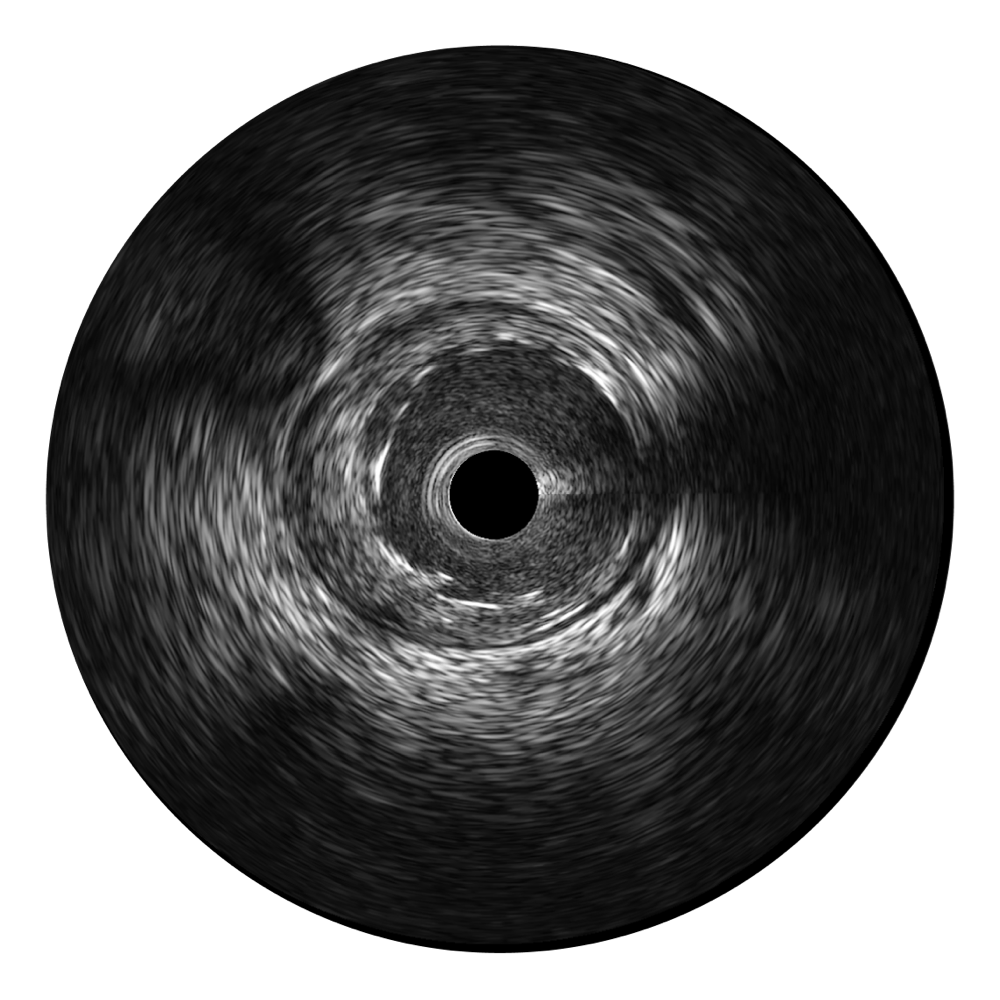

• 传统IVUS图像

对比传统IVUS导管成像,诸侯快讯官网宽频IVUS图像的近场支架梁显影更细腻,远场中膜外血管仍清晰可辨,兼顾远中近,兼顾分辨力与穿透深度